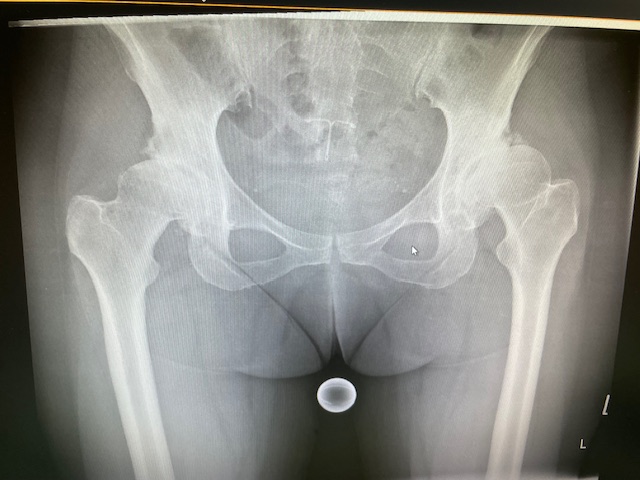

Η ασθενής είχε απευθυνθεί από χρόνια σε πολλούς συναδέλφους ορθοπεδικούς στην Ελλάδα και το εξωτερικό. Είχε προηγηθεί ήδη διεξοδικός απεικονιστικός έλεγχος (ακτινογραφίες λεκάνης και ισχίου, αξονική και μαγνητική τομογραφία).

Το 2024 όταν πλέον η ασθενής απευθύνθηκε σε εμένα, ακολούθησε εκ νέου ακτινογραφικός έλεγχος ώστε να μπορέσει να πραγματοποιηθεί ο προεγχειρητικός ψηφιακός σχεδιασμός του Χειρουργείου.

Ο ακτινογραφικός έλεγχος έδειχνε προχωρημένες εκφυλιστικές αλλοιώσεις και αλλοίωση της ανατομίας της κοτύλης και του μηριαίου.